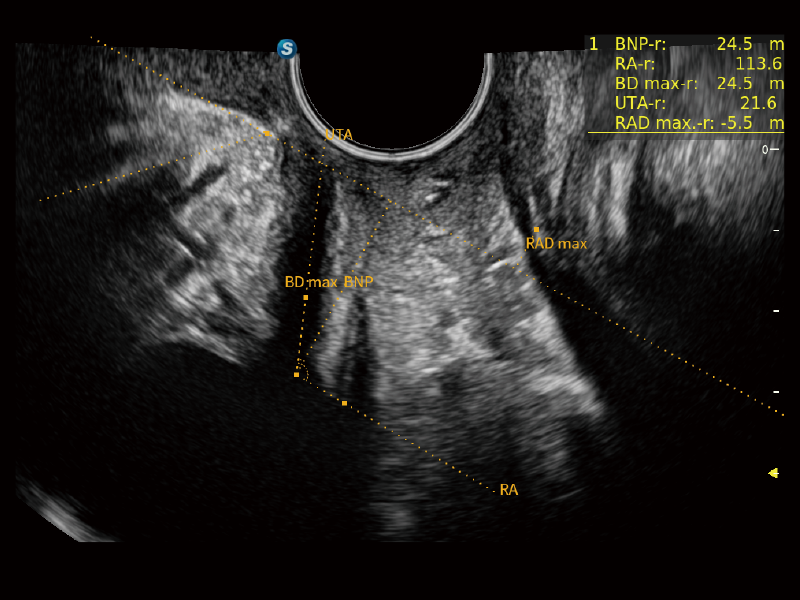

豐富的血流動(dòng)力學(xué)檢測(cè)技術(shù),可在不同醫(yī)療場(chǎng)景中高效捕捉血流信號(hào),助力臨床診療。

在傳統(tǒng)血流的基礎(chǔ)上優(yōu)化掃查和算法策略,能夠更好的抑制組織信息,提煉紅細(xì)胞運(yùn)動(dòng)信息,得到更高幀頻,高靈敏度和分辨率的血流信號(hào),還原更真實(shí)的血流動(dòng)力學(xué)。

通過(guò)創(chuàng)新的Matrix E自適應(yīng)濾波算法,能有效濾除軟組織和噪聲信號(hào),最大限度保留超低速微細(xì)血流的信號(hào);結(jié)合超長(zhǎng)時(shí)間域算法,極大提升細(xì)微血流的敏感性和空間分辨率,更真實(shí)的反應(yīng)組織、包塊的血流灌注情況。